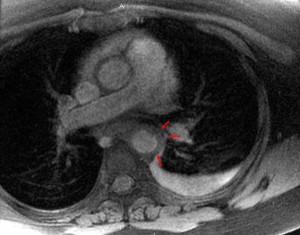

Other imaging studies that are often needed include CTA and MRA.

These methods give more information than duplex about thoracic vessels: